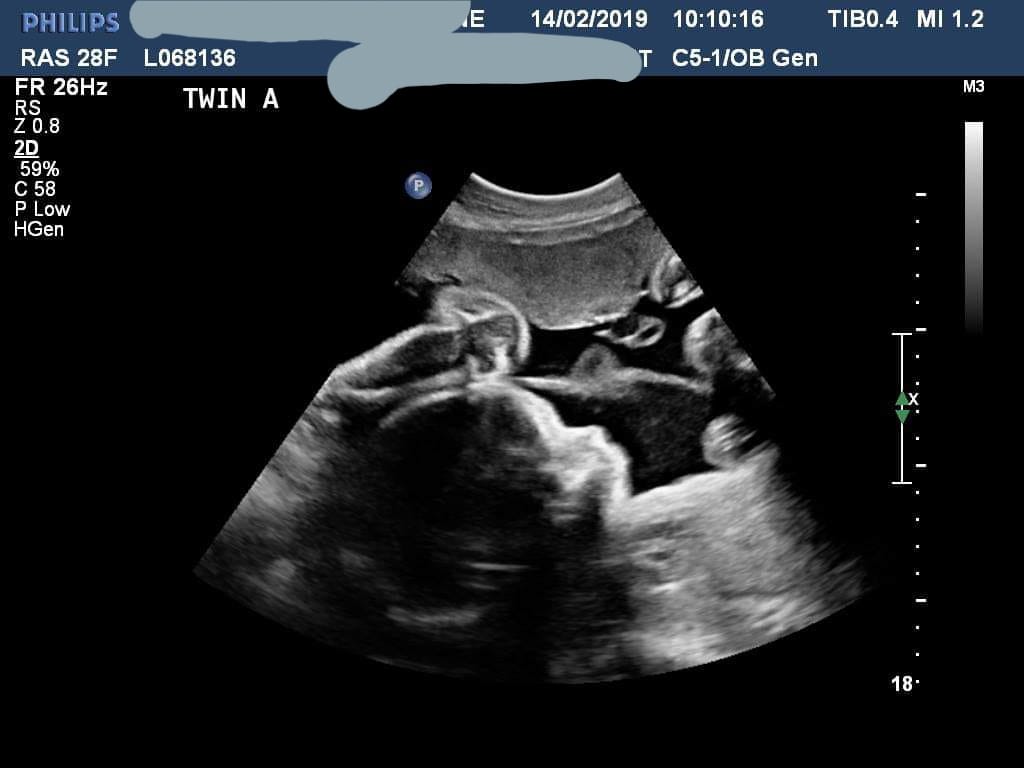

Ultrasound photos at 31 weeks pregnant with twins